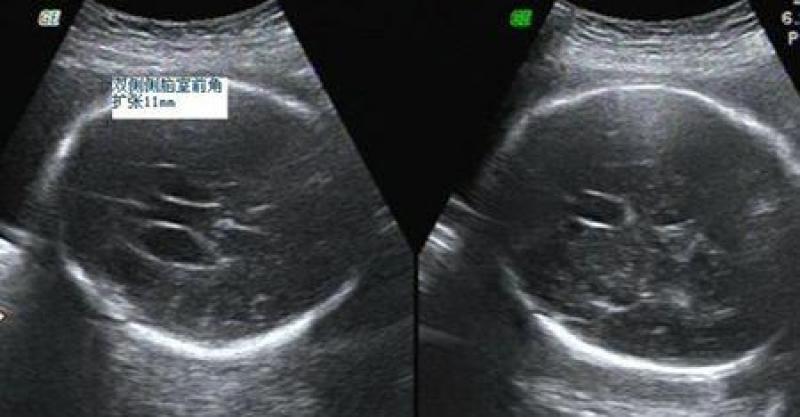

你在媽媽肚子裡26周時,媽媽做了個彩超排畸。記得當時,醫生用探頭透過媽媽的肚皮看了你好久好久,然後用帶著沉重的語氣跟媽媽說:「寶寶側腦室有些增寬。」媽媽當時沒明白這是什麼意思,問醫生:「這個有什麼影響嗎?」醫生說:「左右增寬分別是12mm和13mm,超過15mm就會很危險,屬於腦積水。

」然後給的建議是最好到大醫院去查查看。

媽媽愣住了,有些發矇地拿著報告走出醫院。回到家,第一時間上網查看了關於胎兒側腦增寬的所有資料,了解到胎兒在發育過程中都會有腦脊液過多也就是側腦室增寬的問題,但一般不超過15mm,而且多會自行吸收,有的生出來以後還會吸收,超過15mm就是腦積水,理論上要做引產處理。而你當時的數值已經到了臨界值。

爸爸媽媽都很擔心你,一刻也不敢耽誤,第二天直奔大醫院檢查。同樣是做了彩超,同樣的,醫生用探頭看了你好久好久,得出的結果是:寶寶側腦室,左右增寬分別是12mm和14mm.醫生建議做羊水穿刺。

好不容易等到了孕32周,爸爸陪著媽媽到大醫院做彩超複查,可是結果更糟了,左右側腦室分別是15mm和16mm。醫生反覆檢查了幾次,數值還是一樣,說是達到腦積水的程度了。

其他檢查結果都沒有問題;核磁共振檢查報告顯示腦結構沒有問題,但是側腦室左右寬達到了19mm和18mm。醫生說已經嚴重增寬,情況很不樂觀,最好做引產處理,還說可以馬上給媽媽開引產證明。媽媽提醒醫生:「寶寶的腦結構正常,脊柱和腦中線都沒有問題,而且其他檢查也都沒有問題,難道就不可能生出一個健康的寶寶嗎?」醫生告訴媽媽:很難了,側腦室這麼寬的話始終對腦發育有了損傷了。看來,醫生已經放棄你了。

孕35周時,媽媽又去醫院做了彩超複查,結果顯示左右側腦室分別是16mm和15mm,其餘一切正常。醫生告訴媽媽,是腦積水,要不要留下儘早做決定。媽媽眼淚又下來了。

孕38周,你足月了,媽媽再去複查,醫生說:「增寬有點嚴重,左右側腦室分別是14mm和13mm。」醫生這句話下來,媽媽喜極而泣了,他不知道他說的有點嚴重,對媽媽來說就是天大的好消息,這意味著你開始吸收了嗎?無論如何,媽媽安心了,也不再做任何顧慮,一心等你降臨。